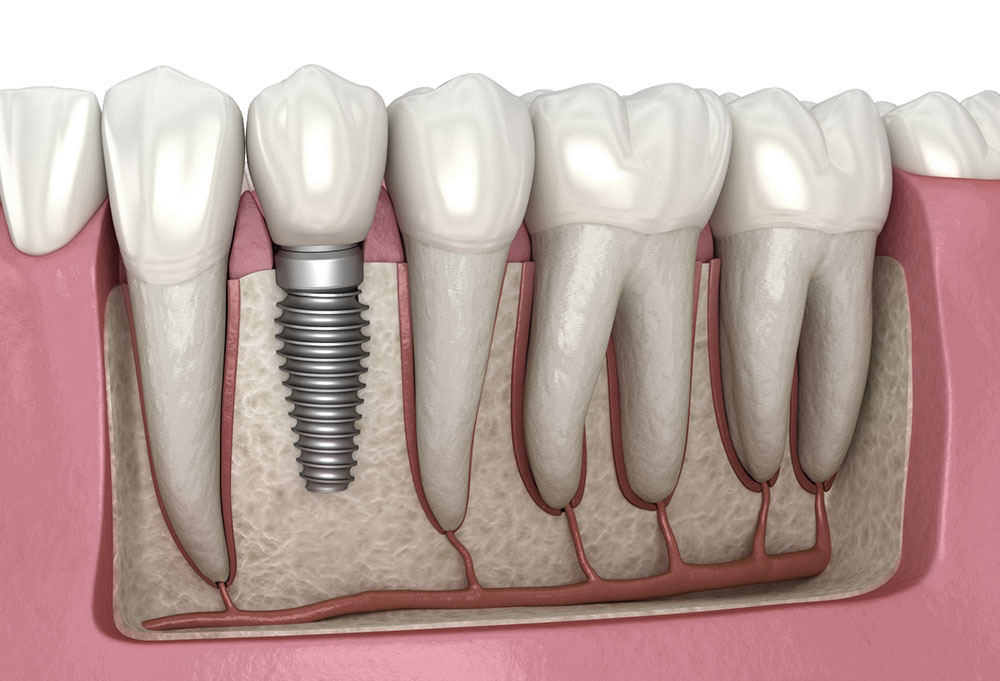

Permanent, natural-looking tooth replacement that restores both the function and aesthetics of missing teeth.

Learn More